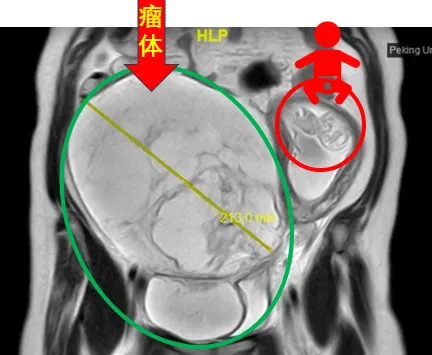

▲2024年4月,谢女士的核磁共振图像显示,巨大肿瘤将她的子宫挤到了腹腔左侧

31岁的谢女士罹患静脉内平滑肌瘤病两年多,正鼓起勇气准备接受治疗时,意外发现自己怀孕了。在孕期激素的“加持”下,谢女士盆腔内的瘤体迅速增大至足月胎儿大小,血管内瘤栓沿着右侧髂静脉、下腔静脉一直“爬”到右心房,甚至在心脏舒张期进入右心室,使她处于随时可能猝死的高危风险下。